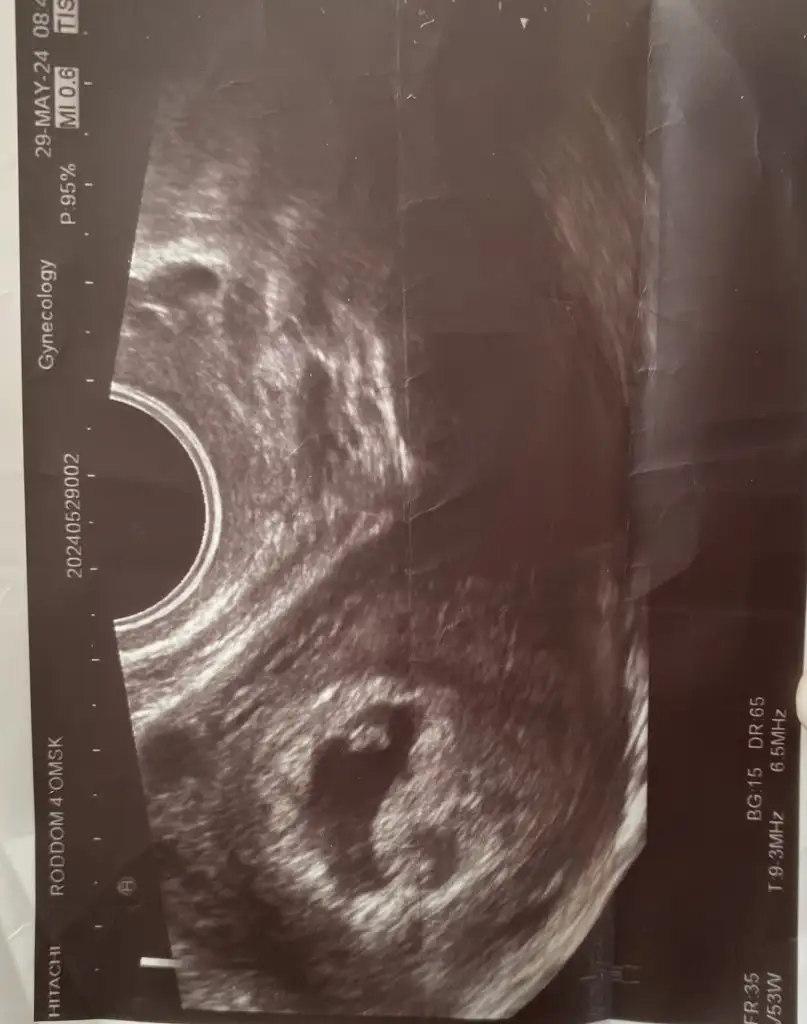

Merhaba benide yorumlarmisinniz?burada 7 haftalık vajinel ultrason diyerinde 12 haftalık